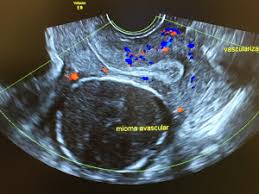

La Radiofrecuencia es una nueva técnica alternativa a la cirugía, que permite destruir y/o reducir casi totalmente los fibromas uterinos, sin requerir ingreso hospitalario y pudiéndose tratar varios miomas en la misma intervención, sin agresión de las paredes uterinas.

La técnica de ablación de miomas por radiofrecuencia, se aplica por vía vaginal a través de una fina aguja que aplica calor en el interior del mioma, lo cual conduce a la necrosis del tejido.